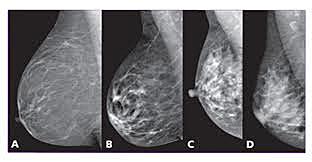

Primeros Estudios de Tumores de Mama

El cirujano alemán Dr. Albert Salomon realizó radiografías en más de 3,000 tumores de mama para identificar los mismos.

• Equipo de Mamografía o Mastografía

Equipo de Mamografía o Mastografía

El francés Charles M. Gross desarrollo el primer equipo de mamografía dedicada exclusivamente al descubrimiento de tumores de mama.